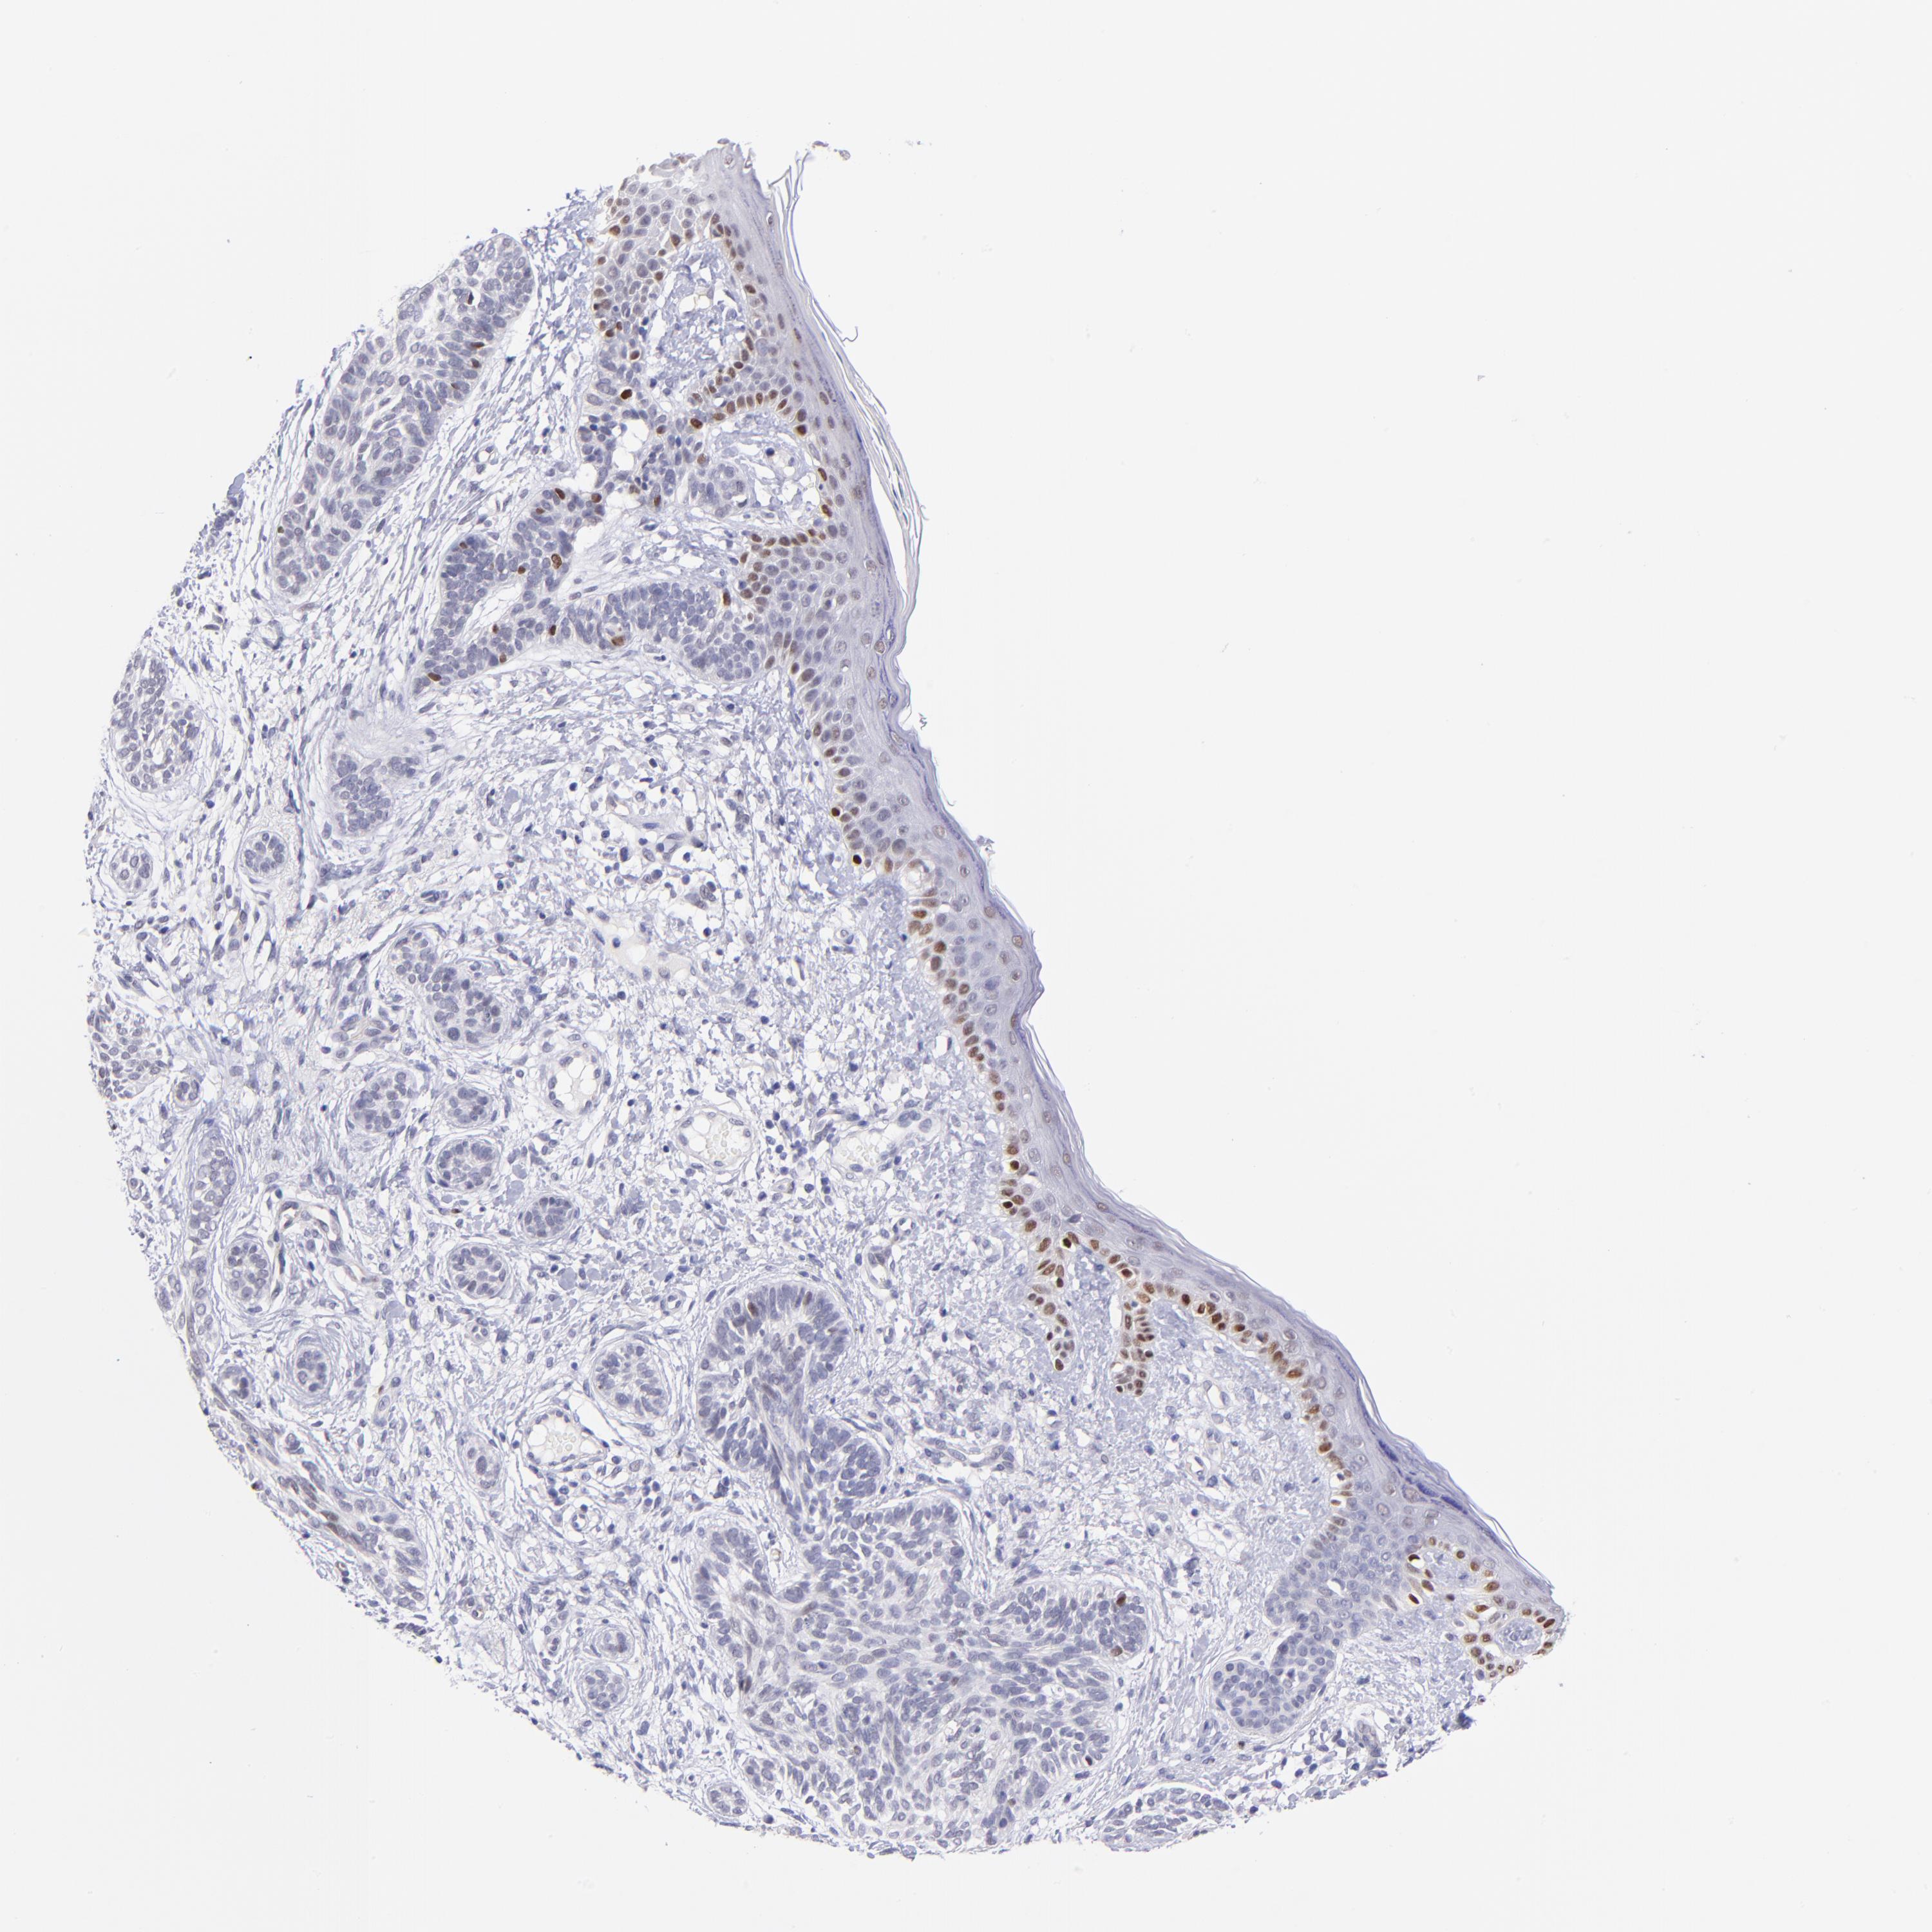

Basal cell and squamous cell cancer

SKIN CANCER - Protein expressioni

A mouse-over function shows sample information and annotation data. Click on an image to view it in a full screen mode. Samples can be filtered based on level of antibody staining by selecting one or several of the following categories: high, medium, low and not detected. The assay and annotation is described here.

Antibody stainingi

Antibody staining in the annotated cell types in the current human tissue is reported as not detected, low, medium, or high, based on conventional immunohistochemistry profiling in selected tissues. This score is based on the combination of the staining intensity and fraction of stained cells.

Each image is clickable and will lead to virtual microscopy that enables deeper exploration of all samples and also displays staining intensity scores, fraction scores and subcellular localization as well as patient and tissue information for each sample.

Antibody HPA001923

Antibody HPA003908

Staining

High

Medium

Low

Not detected

Intensity

Strong

Moderate

Weak

Negative

Quantity

>75%

75%-25%

<25%

None

Location

Nuclear

Cytoplasmic/membranous

Cytoplasmic/membranous,nuclear

Squamous cell carcinoma, NOS

Basal cell carcinoma